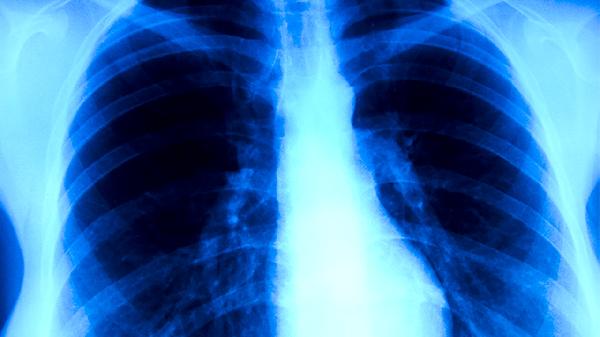

胸部X线检查是肺结核诊断的基本影像学方法,可发现肺部病变的位置、范围和性质。典型肺结核X线表现为上叶尖后段或下叶背段浸润性病变,可能伴有空洞形成。胸部X线检查有助于评估病情严重程度和治疗效果,但不能单独作为确诊依据。对于疑似病例,需要结合其他检查结果综合判断。